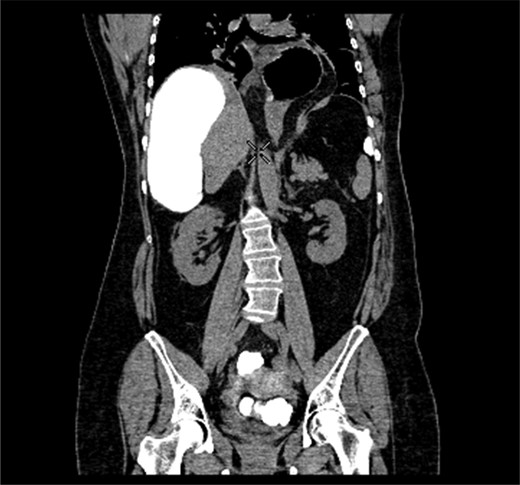

CT coronal section demonstrating caecum medially displacing the liver and causing an upward pressure on the right hemidiaphragm.

Coronal section of contrast-enhanced CT demonstrating contrast filling upwardly displaced caecum.